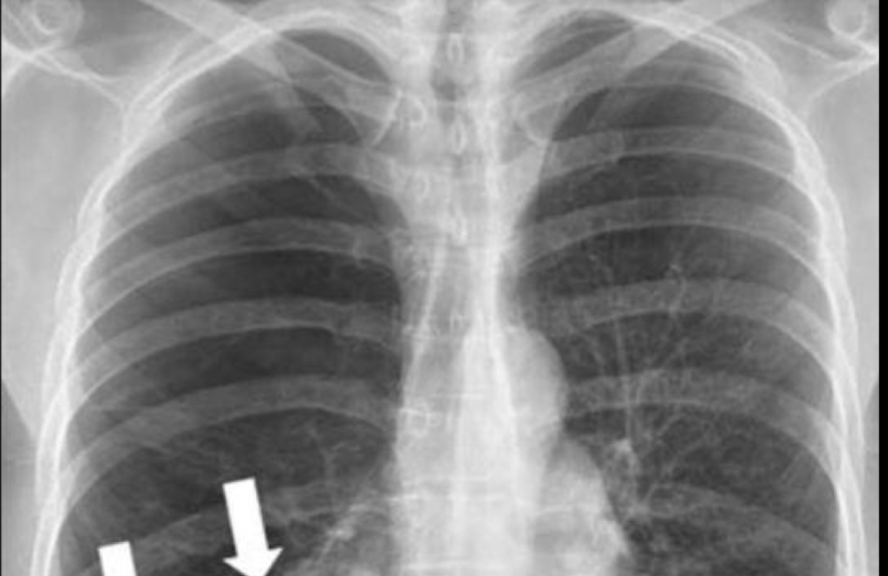

Carácterísticas de la RX en enfisema

A

• Aplanamiento del diafragma

• Disminución de marcas broncovasculares periféricas.

• Hiperlucidez pulmonar

• Bullas

• Corazón en gota

Q

Esta aplanamiento del diafragma con sobreposición del pulmón con el colon nos habla de que enfermedad

Enfisema pulmonar